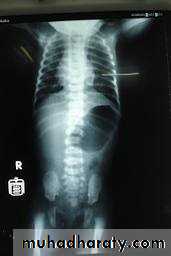

Infantile type :

Usually affect liver, spleen and pancreas , Incompatible with life .

I.V.U.

- Bilateral Large kidney due to numerous small cysts (1-2 mm size ).

- The out-line is not lobulated as in adult.

- I.V.U, may be normal.

- Nephrogram shows minute filling defects.